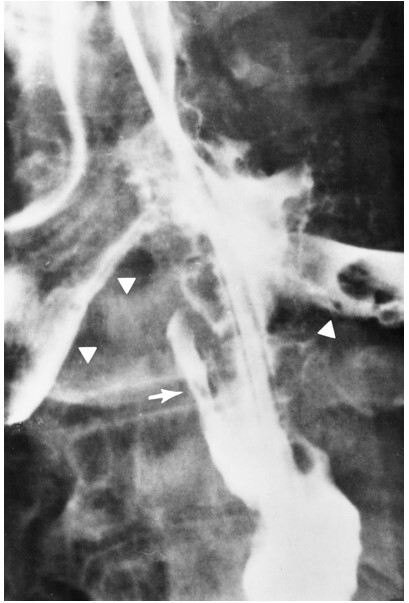

What pathology is shown here?

Tracheaoesophageal fistula

What are the white arrows pointing to?

The airway

What are the radiographic signs of a Tracheoesophageal Fistula?

-Connection of the fistula between airway and esophagus

-Large dilation of the esophagus